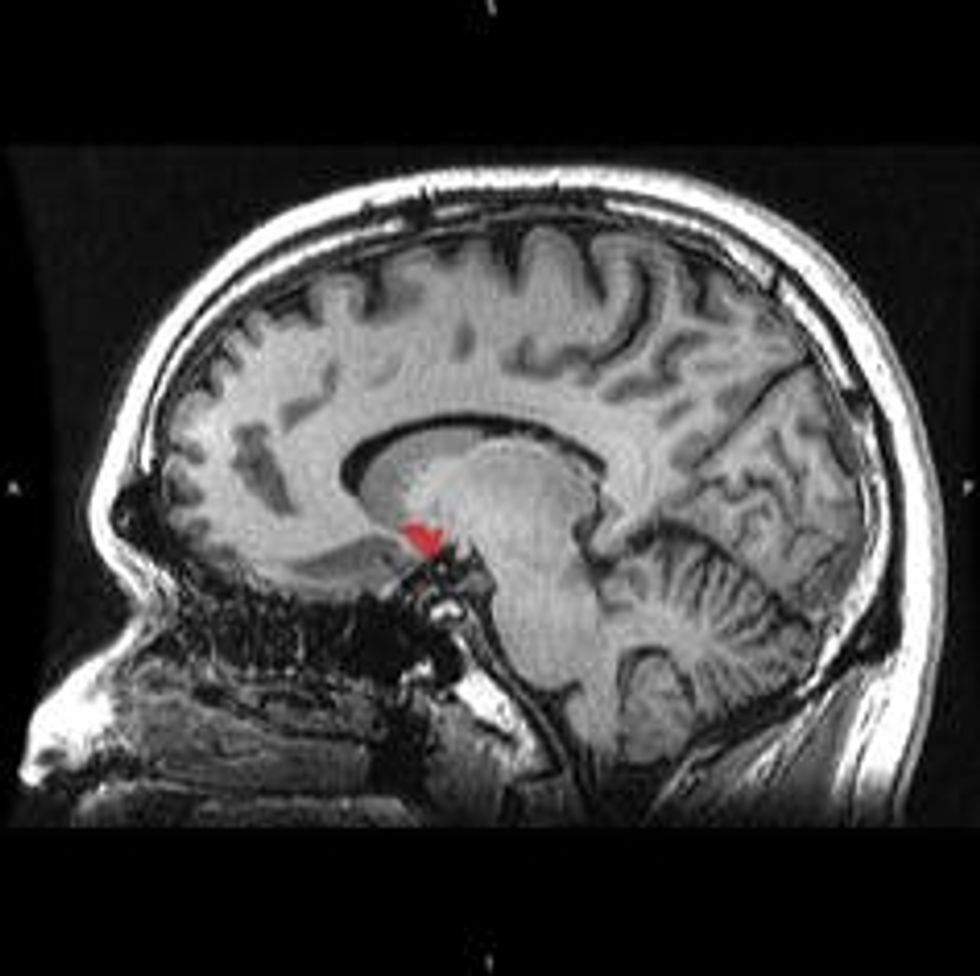

The nucleus accumbens.

Evolution has resulted in the mesolimbic pathway, a brain system that deciphers these natural rewards for us. When we do something pleasurable, a bundle of neurons called the ventral tegmental area uses the neurotransmitter dopamine to signal to a part of the brain called the nucleus accumbens. The connection between the nucleus accumbens and our prefrontal cortex dictates our motor movement, such as deciding whether or not to taking another bite of that delicious chocolate cake. The prefrontal cortex also activates hormones that tell our body: “Hey, this cake is really good. And I’m going to remember that for the future.”